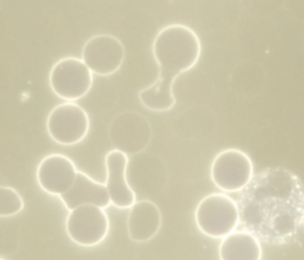

In this video we observe a red blood cell under darkfield microscopy.At first, two bright inclusions can be seen inside the cell — unusual structures not found in healthy red cells. As time passes, these inclusions…